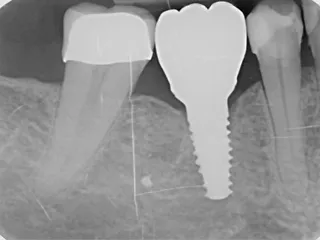

• Control radiográfico después de la inserción de los implantes dentales.

• Radiografía de la corona definitiva sobre el pilar Variobase® atornillada en la posición final.